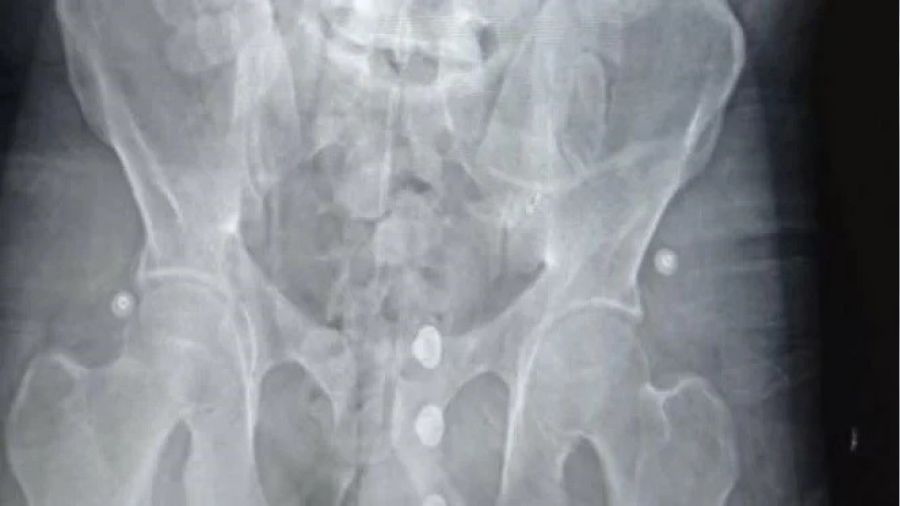

Türkiye'ye midesinde uyuşturucu maddeleri soktuğu tespit edilen zanlı ardından Yalova Devlet Hastanesi'ne götürüldü. Tomografi cihazı ile gerçekleştirilen iç beden görüntüleme muayenesinde mide ve bağırsaklarında çok sayıda kapsül olduğu tespit edildi. Şüphelinin sağlık durumu da göz önünde bulundurularak 3 gün hastanede tutuldu.

Tıbbi gözlem süreci boyuncu sürdürülen çalışmalar neticesinde zanlının mide ve sindirim sisteminde bulunan 155 adet kapsül reçine esrar daha çıkarıldı. Fas'ta yutarak midesine yerleştirdiği 194 kapsül halindeki 1 kilo 545 gram reçine esrarı Türkiye'ye getiren zanlı sevk edildiği mahkemece tutuklanarak cezaevine gönderildi.